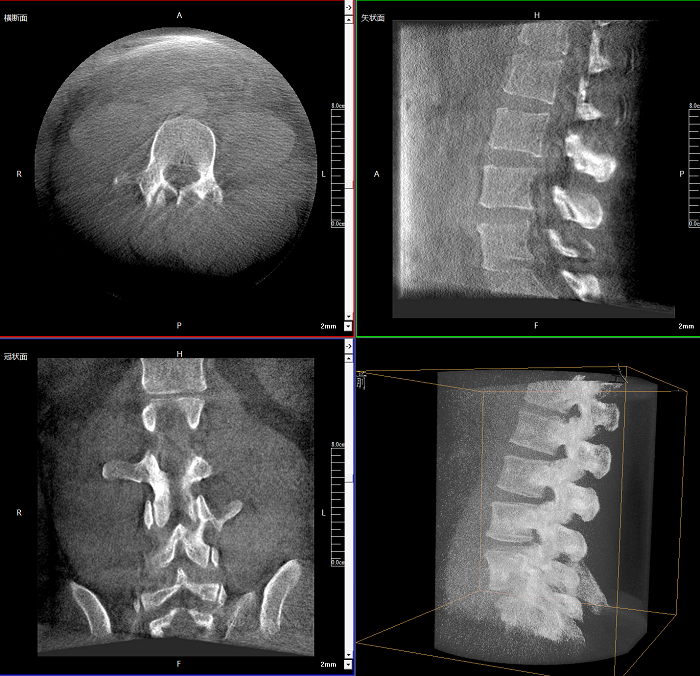

三維成像 全面觀察

任意視角、任意切面觀察

術中實時生成橫斷面、矢狀面、冠狀面及三維影像,可在任意切面、任意角度評估植入物和解剖結構的相對位置。